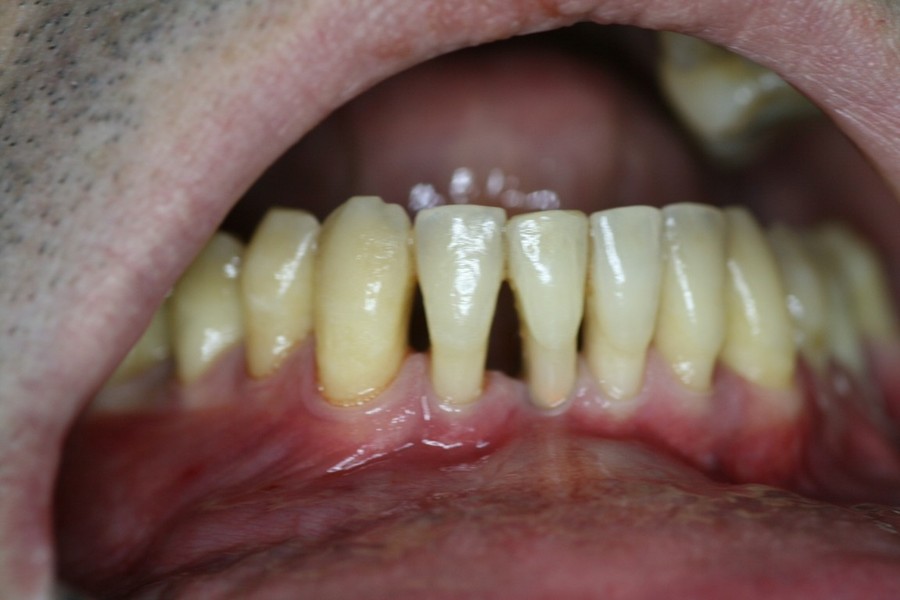

Chirurgia plastica Muco-Gengivale